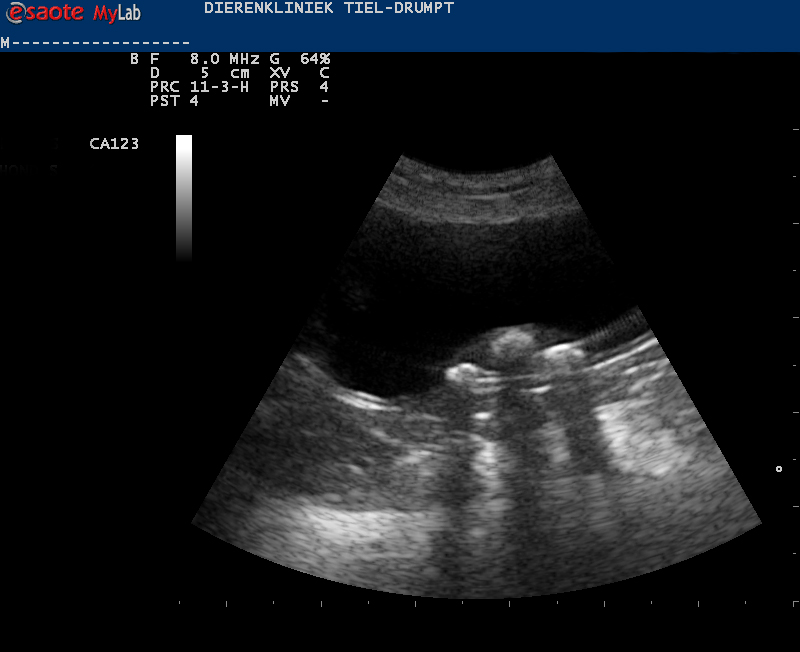

De diagnose

De diagnose van blaasgruis en blaasstenen wordt meestal gesteld via verder onderzoek. Er wordt gestart met een urineonderzoek en met een therapie. Soms is dit onvoldoende om het probleem op te lossen en is er een echo nodig. Met deze echo kan er beter gekeken worden naar de inhoud van de blaas, hoe de blaaswand er uitziet en er kan een punctie gedaan worden van de urine, voor een eventueel bacterieel onderzoek.